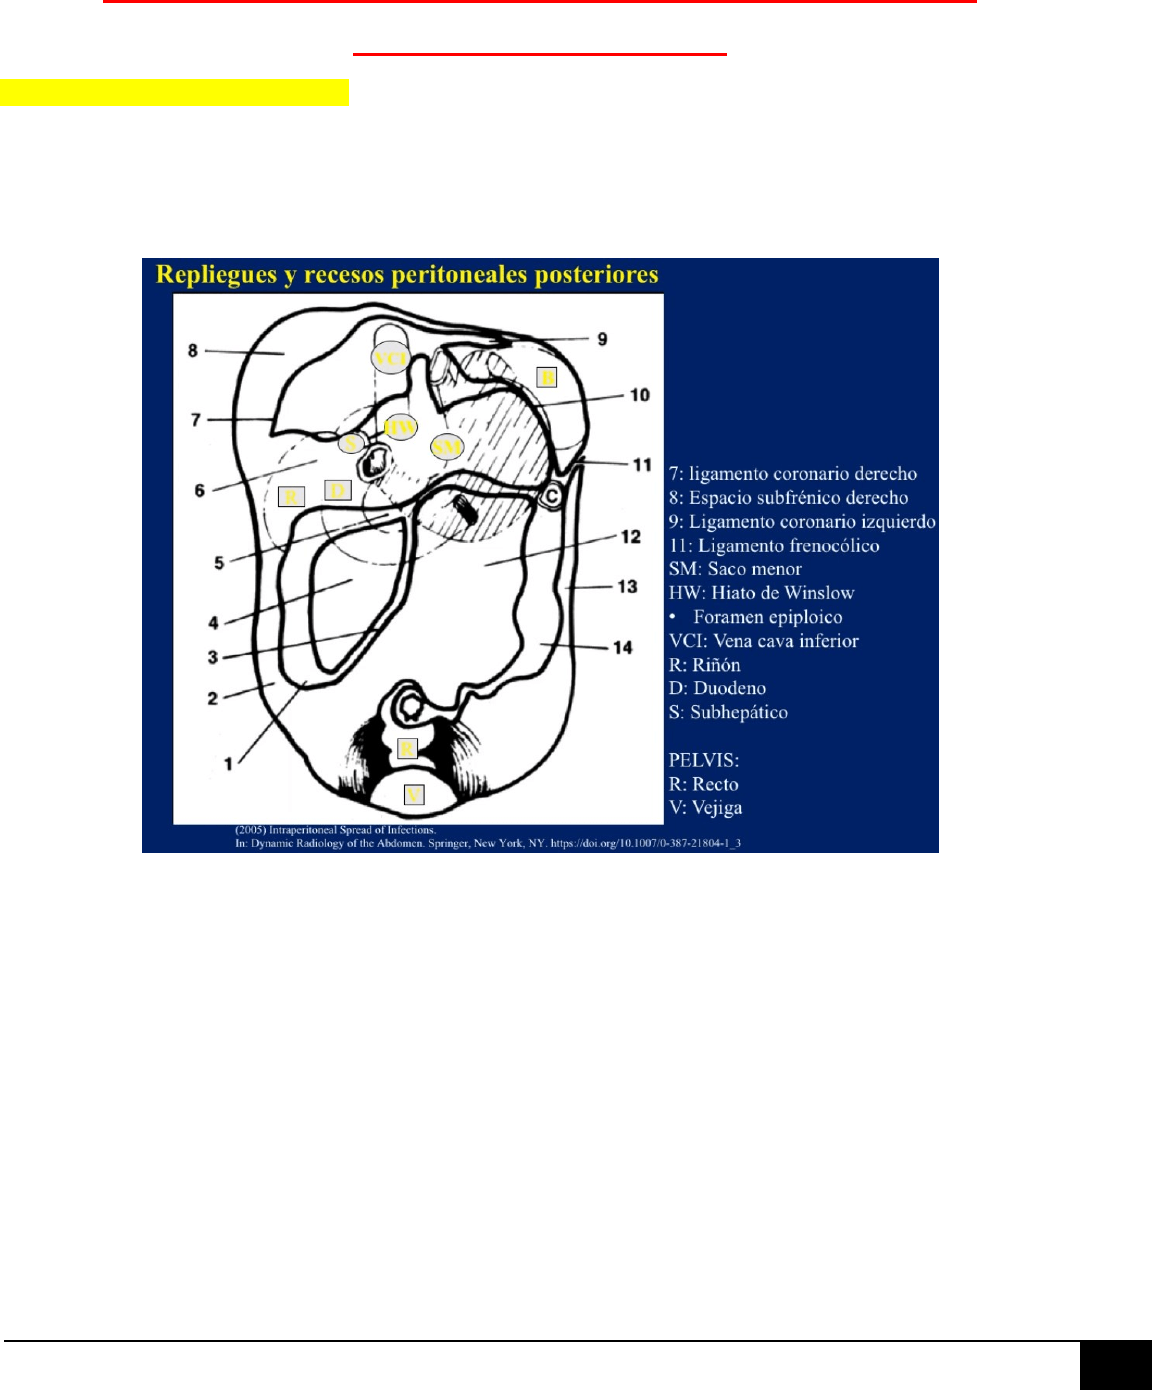

ESPACIOS

SUPRAMESOCÓLICOS

ESPACIO SUBFRÉNICO

IZQUIERDO:

Separado del derecho a

través del ligamento

falciforme.

ESPACIO PERIHEPÁTICO

DERECHO

1.- ESPACIO

SUBFRÉNICO

DERECHO:

Localizado entre la superficie hepática y

el diafragma, a la derecha del LF. Está

limitado posteriormente por la reflexión

superior del LCD y LTD, que lo separan

del espacio subhepático derecho.

2.- ESPACIO SUB-

HEPÁTICO DERECHO:

ANTERIOR: Situado inmediatamente

posterior a la porta hepatis y

comunicado con el saco menor a través

del foramen epiploico.

POSTERIOR o “FOSA DE MORRISON”:

Espacio más declive del abdomen en el

paciente en decúbito supino y, por

tanto, un sitio frecuente de acúmulo de

líquido, hemoperitoneo, metástasis y

abscesos. Está separado del espacio

subfrénico derecho por el LTD, pero

ambos espacios comunican libremente

entre sí alrededor del borde del LTD.

SACO MENOR O

TRANSCAVIDAD DE LOS

EPIPLONES

Situado por detrás del epiplón menor, el estómago y el bulbo

duodenal, y del LGC. Posteroinferiormente está limitado por el MT,

lateralmente a la izquierda por los LGE y LER. Su límite posterior viene

definido fundamentalmente por la mayor parte del páncreas.

Comunica a la derecha con el resto de la cavidad peritoneal a través

del foramen epiploico o hiato de Winslow. Puede verse ocupado por

ascitis benigna o maligna; sin embargo, cuando una colección líquida

aislada se localiza en el saco menor, debemos pensar en pancreatitis o

en una úlcera gástrica o duodenal perforadas